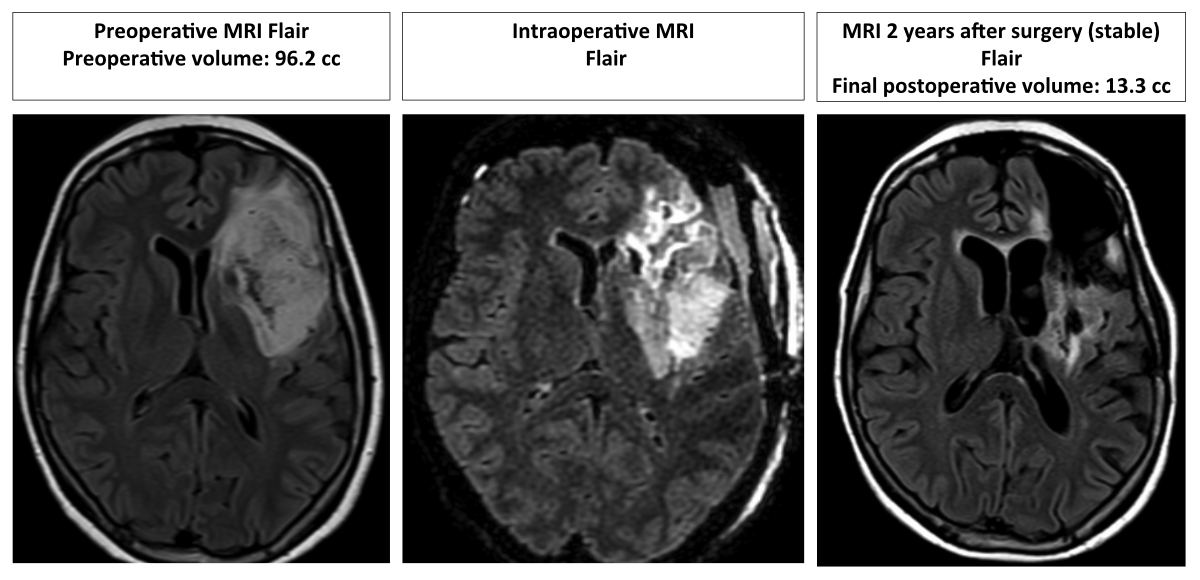

At the last follow-up, 12 (12/13, 92.3%) patients had volumetric tumour stability or a decreased volume. One (7.7%) patient with oligoastrocytoma WHO II required further surgery at 21.6 months after the first resection due to volumetric progression and drug-resistant epilepsy, with LPFS achieved (see figure 5).

Figure 5 Illustrative case of an oligodendroglioma WHO II, 1p19q co-deleted.